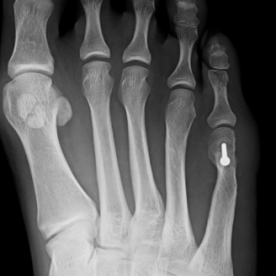

12) Hallux valgus

Häufigste und bedeutendste Zehendeformität mit seitlicher Abweichung der Großzehe im Grundgelenk. Es findet sich eine häufige Kombination mit einer Hammer- und Krallenzehe. Die konservative Therapie, meist im Frühstadium, umfasst die Druckentlastung des Großzehenballens, Barfußlaufen, ringförmige Schaumstoffpolster und Einlagenversorgung.

In fortgeschrittenen Fällen ist in der Regel eine operative Therapie mit Stellungskorrektur der Großzehe notwendig.